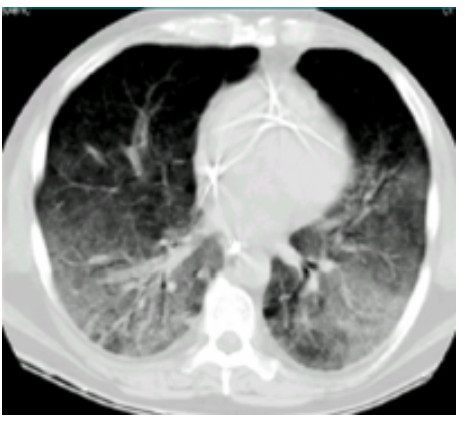

SAP发生呼吸衰竭的原因很复杂,其原因有以下几种。(1)SAP因为炎症反应导致的ARDS(图 1),这是普遍认为的一种原因,但实际上ARDS在SAP患者呼吸衰竭中很多时候是非主要原因。SAP急性期虽然病情进展很快,出现多脏器功能损伤,甚至休克,有类似于脓毒症和感染性休克样的表现,但其炎症反应并不如脓毒症这么强烈,大量的研究可见SAP发生过程其IL-6很少过千,而脓毒症则IL-6动辄大于5 000或10 000,SAP两肺影像学也很少有典型的非心源性肺水肿的双侧阴影,超声下也很少有“B线”表现。但胆道感染引起的脓毒症合并SAP的患者,其ARDS发生率会明显上升。现在随着高脂血症胰腺炎的增加,部分患者到院时同时存在糖代谢障碍,合并有糖尿病酮症,入院前后出现糖尿病酮症昏迷,有些患者会伴有呕吐误吸或者插管时误吸,这类患者在急性期会出现误吸相关的ARDS。(2)SAP是腹腔重症的一种,急性期因为腹膜后急性胰周液体积聚和急性胰周坏死物积聚,导致腹腔压力进行性升高,随之出现横膈抬高,两肺压缩,从而导致“小肺”,这和ARDS的“baby lung(小肺)”不同(图 1: ARDS;图 2、3: 腹内压14 mmHg和23 mmHg的对比,明显看到图 3呈现横膈抬高引起的小肺)。因横膈位置上抬导致小肺是SAP呼吸衰竭的主要原因。(3)两下肺不张(图 4)和胸腔积液(图 5):这两个原因也是导致SAP呼吸衰竭的主要原因,因为膈下刺激,导致两下肺的不张和大量胸腔积液常见于SAP患者,这两种原因导致的呼吸衰竭也和ARDS不同。(4)其他原因:胸腔出血、肺梗死和气胸亦可见于SAP相关呼吸衰竭,但相对少见。

| 图 3 腹内压23 mmHg |